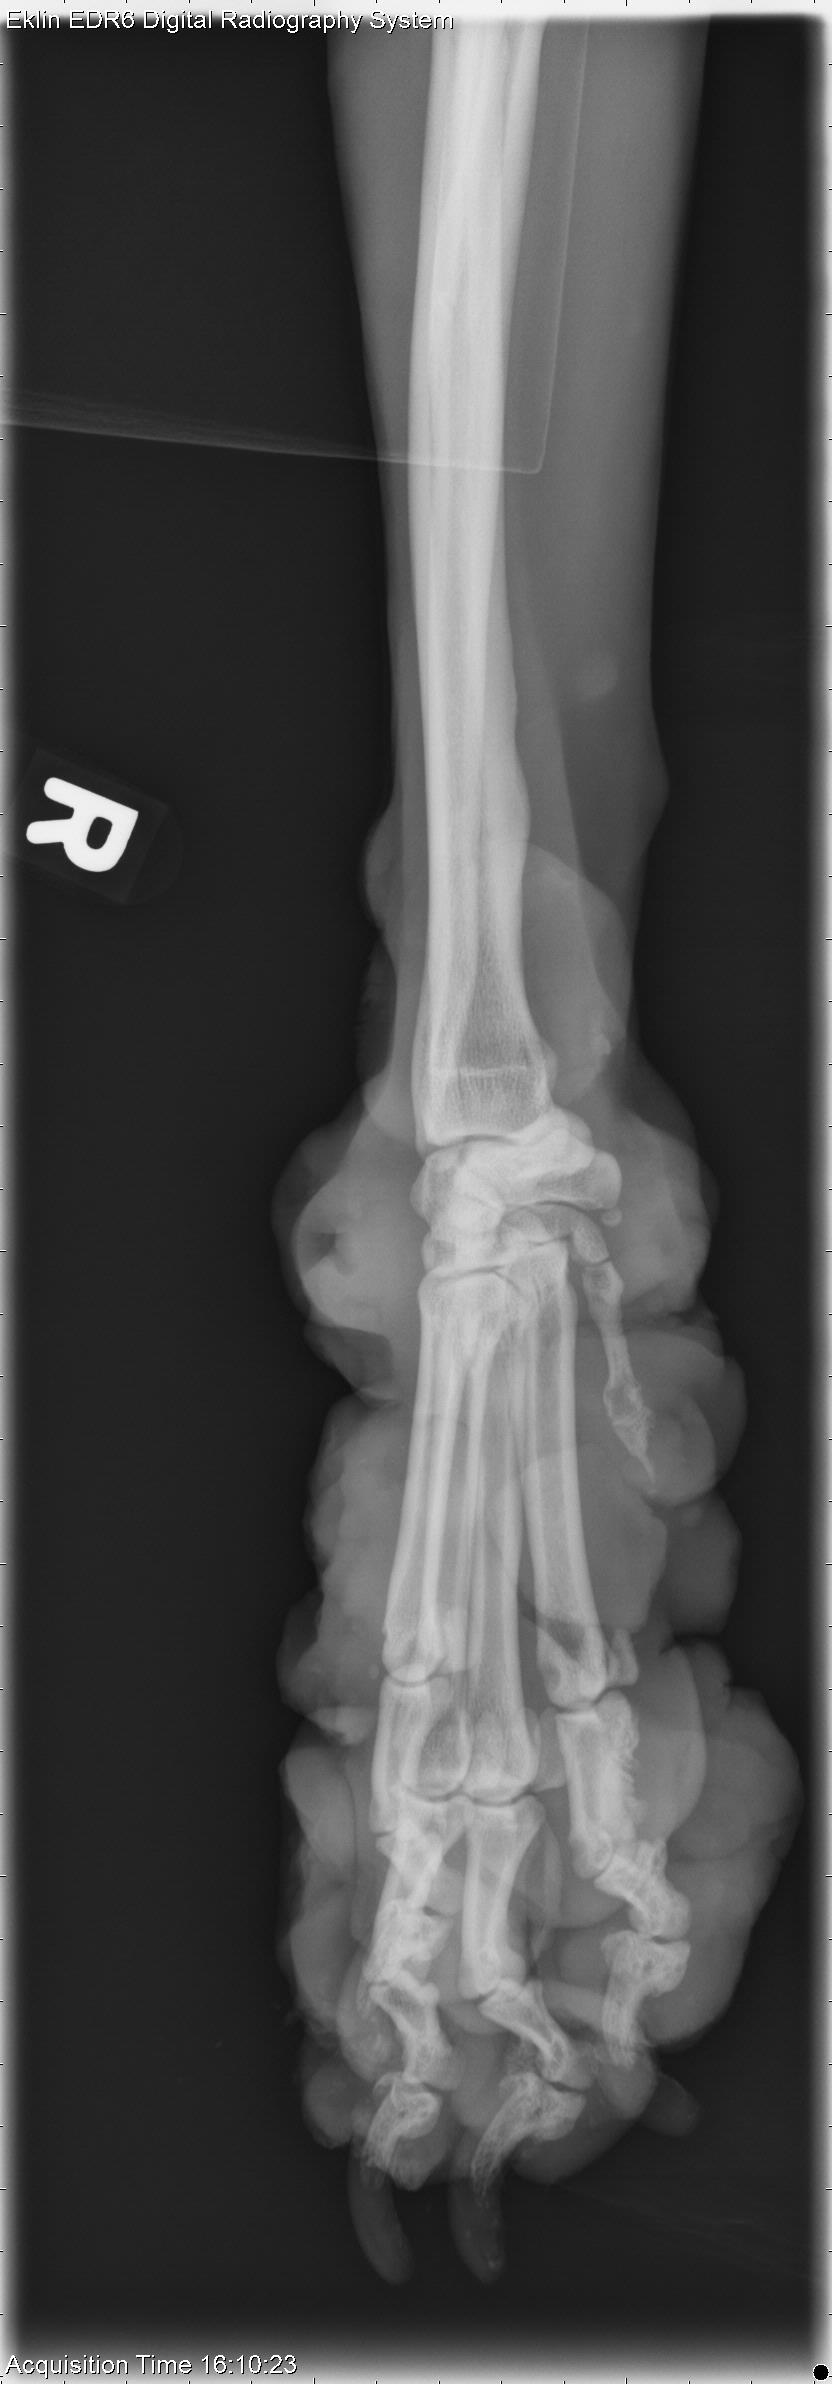

The last case of the year is 10-year-old male Boxer with swelling on the thoracic wall and right thoracic limb. What are your findings and differential diagnoses?

Thoracic Limb-R AP Fore

Thoracic Limb-R LAT Fore

There are multiple thickened regions of soft tissue surrounding the right carpus. Many of these swellings have air-filled cavities on the surface indicating ulceration. There is irregular to pallisading periosteal new bone formation along the medial aspect of the proximal phalanx of the second digit. The phalanx of the first digit is irregularly margined and tapers to a sharp osseous projection, with a small mineral opacity seen just distal to this phalanx. There is smoothly margined periosteal new bone formation along the medial aspect of the mid-diaphysis of the right 3rd metacarpal bone. There is also smoothly margined, periosteal new bone formation along the mediocaudal aspect of the distal radial diaphysis.

The soft tissue changes are consistent with neoplasia, likely an additional site to that seen on the thoracic wall. The ulceration may have resulted in osteomyelitis, or periostitis of the adjacent bone. Neoplastic extension into the bone could also be considered.

• Non-epitheliotrophic cutaneous T-cell lymphoma (large cell)